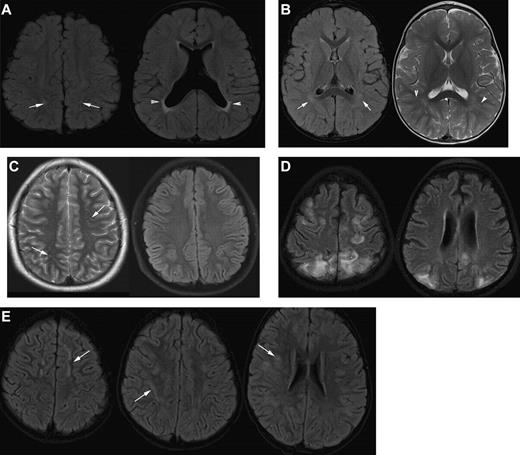

MRI in sickle cell disease. (A) Coronal T1-weighted MRI, (B) coronal T2-weighted MRI, and (C-H) axial T2-weighted MRI in patients with homozygous SCA. (A-C) Silent cerebral infarction (white arrows) in the parietal white matter in a 10-year-old girl with headache. (D) Three years later, there is progressive atrophy on MRI in the context of intermittent ataxia and squint. (E-H) Four cases associated with acute illness. (E) Silent cerebral infarction (black arrows) in the watershed regions between the anterior, middle, and posterior regions, including the deep white matter, in a patient who had previously had posterior reversible encephalopathy syndrome in the context of cyclosporine treatment for nephrotic syndrome. (F) Bilateral watershed infarction in a child who had seizures in the context of a facial infection. Motor examination was normal but his IQ was reduced by 30 points compared with premorbid testing. (G) Encephalomalacia after sagittal sinus thrombosis secondary to pneumococcal meningitis. (H) Occipital infarction after acute chest crisis. A homonymous visual field defect was detected after the infarct was noted on MRI.

In the first systematic study of SCI in adults with SCA, Vichinsky et al used a definition of a minimum of 5 mm signal hyperintensity in the T2-weighted image,9 but to be included, lesions also had to show corresponding hypointensity on the T1-weighted image (Figures 1E, 2A). Normal adults typically accumulate T2 hyperintensities as they age, but children do not. This more restrictive definition of SCI and the distinction from encephalomalacia and atrophy (Figures 1H, 2D-H) parallels the descriptions used in general populations of asymptomatic elderly adults with SCI.10

Strict guidelines for radiographic assessment of SCI require the ability to distinguish SCI from acute and chronic mimics of SCI (Figure 4). Because of the possibility of misclassification of a diagnosis of SCI when a new lesion is suspected, a dialogue between the neuroradiologist, neurologist, and hematologist should occur so both the clinical history and differential diagnoses can be carefully considered.

As is required by this definition, children with SCI do not have any obvious evidence of symptoms, other than perhaps academic or behavioral difficulties. Quite often, the presence of SCI is detected when the child presents with subtle neurologic findings prompting a brain MRI. The neuroradiologist may identify additional previous infarcts and distinguish an acute cerebral infarct from a previously unknown SCI (Figure 3A). A focal DWI hyperintensity indicates an ischemic injury within the last 8 to 10 days14 (Figure 3B), while the presence of brain atrophy suggests a chronic process.